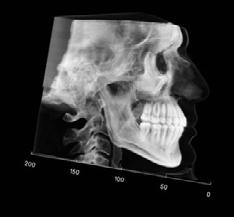

Clinical evaluation showed a mild Class III skeletal pattern with a constricted maxilla, mildly dolichofacial and straight

profile (Figure 1). Full adult dentition was present with all third molars extracted. Maxillary and mandibular incisors were normoclined. The maxillary midline coincided with the facial midline, and the mandibular midline was 2 mm to the right of the facial midline. There was a 2 mm to 5 mm lateral open bite on the right side from the second molar to the lateral incisor, and the maxillary occlusal plane was canted to the left of the interpupillary line. A lateral tongue thrust into the open bite was noted on swallow.

The right side was in posterior crossbite and there was an edge-to-edge anterior bite with wear on the maxillary central incisors. Mild gingival recession was noted, but soft tissue was generally within normal limits. CBCT analysis found no radiographic evidence of osteoarthritis in the TMJ joints, nor osseous or apical pathology involving the maxillary or mandibular teeth. His airway was not constricted. Initial report from the myofunctional therapist indicated that the patient never developed a mature swallow sequence and had a bilateral posterior tongue thrust.

Figure 1. Initial records.